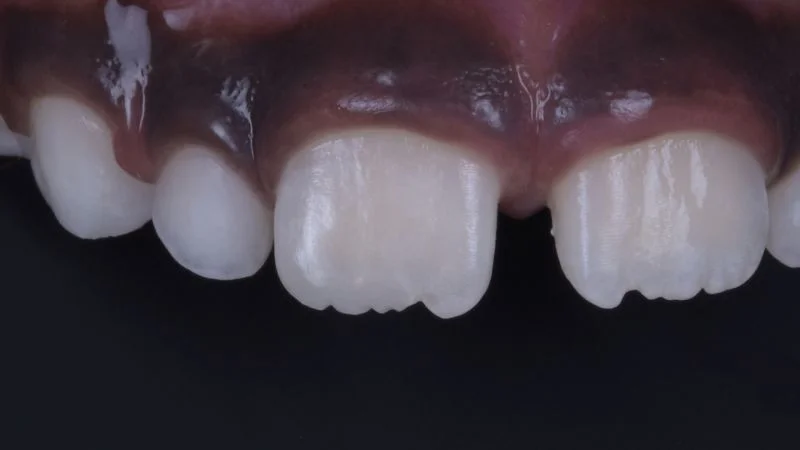

Finger Index Technique.

Ein Finger dient als Grundlage für die Applikation von 3M Filtek Easy Match Universal Komposit im Farbton Bright zur Wiederherstellung der Form, Kontur und Ästhetik.

Restauration mit Komposit.

Freihand-Modellation der Komposit-Restauration.